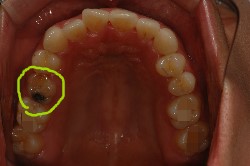

연두색으로 동그라미 친 위 왼쪽 하나, 아래 양쪽 하나씩

게다가 위쪽에 잇는 유치는 공기주머니가 치아뿌리 바로 위까지 내려와 잇어서

만에하나 얘도 빠진다면 임플란트 할때 공기주머니를 올려주는 수술을 또 해야한다는 겁니다